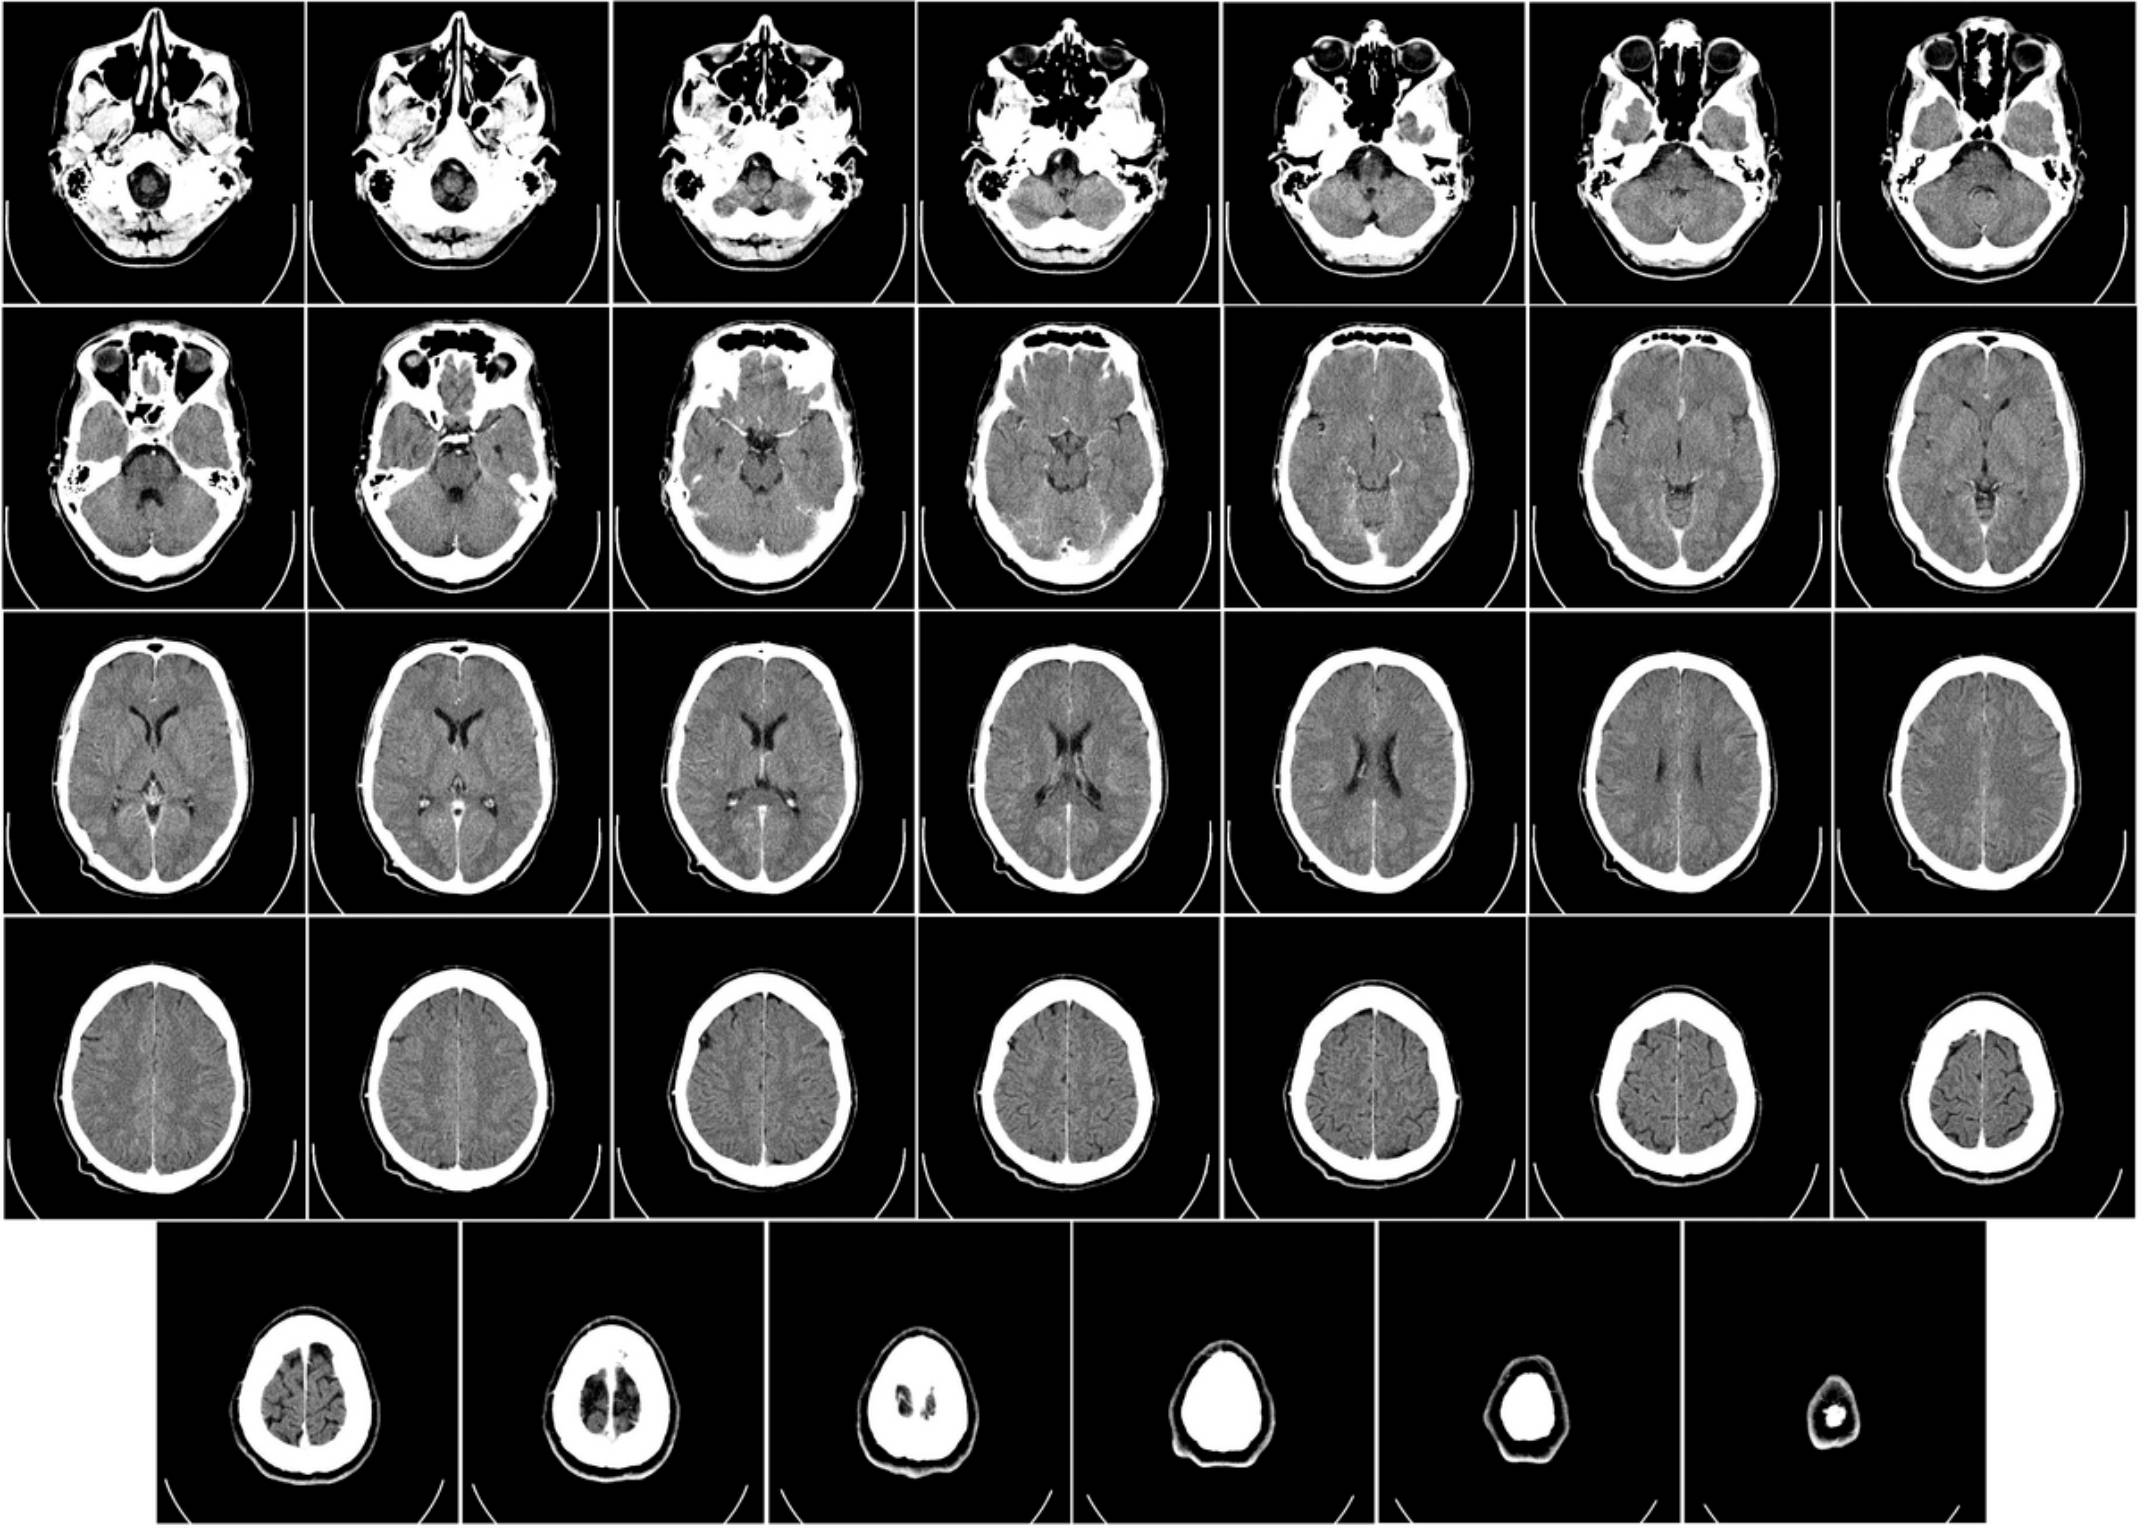

2. كومپيۇتېر توموگرافىيەسى (CT) – بەدەننى «تىلىملاپ» تەكشۈرۈش

CT بولسا رېنتىگېننىڭ تەرەققىي قىلغان شەكلى بولۇپ، «ئادەمنى توغراپ كۆرۈش» دەپ چۈشىنىشكە بولىدۇ (ئەلۋەتتە رەسىمدە).

CT تېخنىكىسى 1970-يىللارنىڭ بېشىدا ئەنگىلىيەلىك ئىنژېنېر گودفرېي خائۇنسفىلىد (Godfrey Hounsfield) ۋە جەنۇبىي ئافرىقىلىق فىزىكا ئالىمى ئاللان كورماك (Allan Cormack) تەرىپىدىن كەشىپ قىلىنغان. دۇنيادىكى تۇنجى CT ماشىنىسى 1971-يىلى لوندوندا رەسمىي ئىشلىتىلىپ، بىر بىمارنىڭ مېڭىسى تەكشۈرۈلگەن. بۇ تېخنىكا ئەنئەنىۋى رېنتىگېن بىلەن كومپيۇتېر ھېسابلاش تېخنىكىسىنى بىرلەشتۈرۈپ، بەدەننىڭ ئىچكى قۇرۇلمىسىنى 3 ئۆلچەملىك ۋە قاتلاملىق كۆرۈش ئىمكانىيىتىنى ياراتقانلىقى ئۈچۈن، تېبابەت ساھەسىدە زور ئىنقىلاب ھېسابلىنىدۇ، بۇ ئىككى ئالىم 1979-يىلى نوبېل تېببىي مۇكاپاتىغا ئېرىشكەن.

- ئىشلەش پرىنسىپى: كۈچلۈك X نۇرى بەدەننى ئايلىنىپ تەكشۈرىدۇ ۋە كومپيۇتېر ئارقىلىق بەدەننىڭ ھەر بىر قەۋىتىنى (تىلىم-تىلىم قىلىپ) رەسىمگە ئالىدۇ. بۇ ئارقىلىق ئۈچ ئۆلچەملىك (3D) تەسۋىر ھاسىل قىلغىلى بولىدۇ.

- ئەڭ ماس كېلىدىغان ئورۇنلار:

- جىددىي قۇتقۇزۇش: ماشىنا ۋەقەسى ياكى يىقىلىپ چۈشۈش سەۋەبىدىن باش سۆڭەك، كۆكرەك ۋە قورساق قىسمىدىكى ئىچكى قاناش ياكى سۇنۇقلارنى تېز سۈرئەتتە كۆرۈش ئۈچۈن.

- ئۆپكە ۋە كۆكرەك: ئۆپكىدىكى كىچىك تۈگۈنچىلەر، ئۆسمىلەرنى بايقاشتا رېنتىگېندىن كۆپ ئۈستۈن تۇرىدۇ.

- مۇرەككەپ سۆڭەك سۇنۇقلىرى: ئىنچىكە سۆڭەك قۇرۇلمىلىرىنى كۆرۈش ئۈچۈن.

- ئارتۇقچىلىقى: تەسۋىرى ناھايىتى ئېنىق، قاتلاممۇ-قاتلام كۆرسىتىپ بېرىدۇ. تەكشۈرۈش سۈرئىتى تېز.

كومپيۇتېر توموگرافىيەسى (CT) نىڭ كەمچىلىكى:

- يۇقىرى رادىئاتسىيە: رېنتىگېنگە سېلىشتۇرغاندا رادىئاتسىيە (نۇرلىنىش) مىقدارى نەچچە ئون ھەسسە يۇقىرى بولىدۇ. كۆپ قېتىم چۈشۈش تەۋسىيە قىلىنمايدۇ.

- بۆرەككە يۈك: قان تومۇرنى ئېنىق كۆرۈش ئۈچۈن «كۈچەيتكۈچى دورا» (Contrast dye) ئىشلىتىشكە توغرا كەلسە، بۇ دورا بۆرەك ئىقتىدارى ئاجىز بىمارلارغا زىيان قىلىشى ياكى سەزگۈرلۈك پەيدا قىلىشى مۇمكىن.

- يۇمشاق توقۇلمىلار چەكلىك: پەي ۋە مۇسكۇل زەخىملىنىشىنى كۆرۈشتە MRI غا يەتمەيدۇ.

- ھامىلىدارلارغا تارتىلمايدۇ!